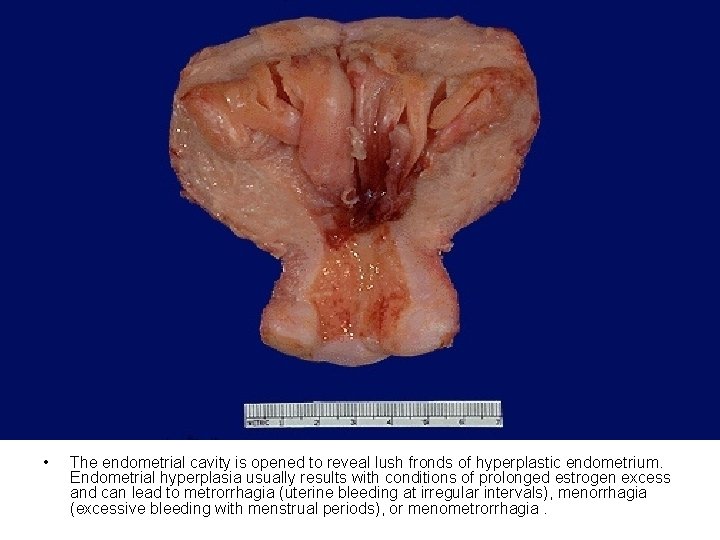

• The endometrial cavity is opened to reveal lush fronds of hyperplastic endometrium. Endometrial hyperplasia usually results with conditions of prolonged estrogen excess and can lead to metrorrhagia (uterine bleeding at irregular intervals), menorrhagia (excessive bleeding with menstrual periods), or menometrorrhagia.